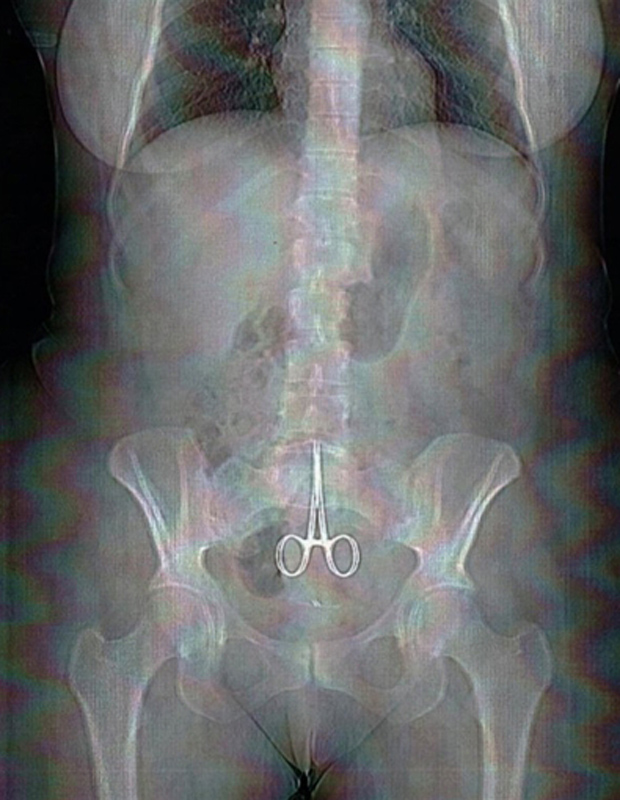

Médico e hospital foram condenados a pagar R$ 30 mil por danos morais Fonte | TJMG O aposentado L.L.S., de...